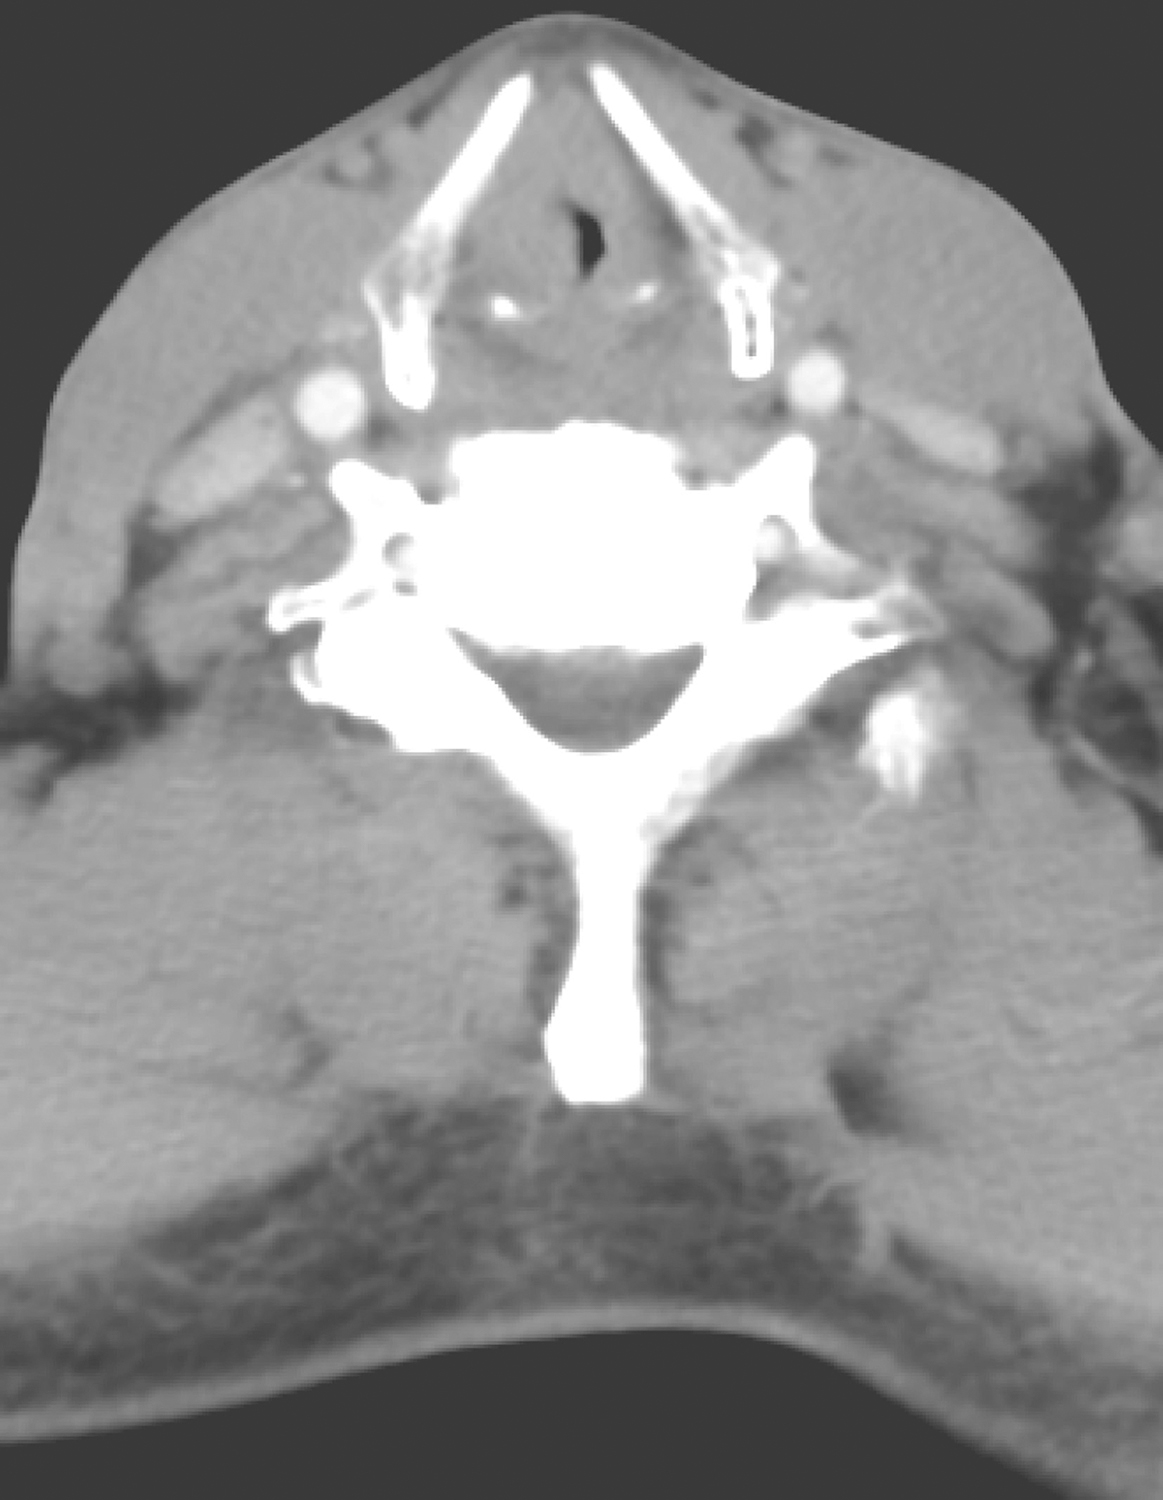

2.2018年3月1日颈胸CT

显示:右侧假声带、前联合不规则增厚并强化,右声带均匀增厚,左侧声带未见明确异常,喉室变小(图2)。双侧颈深链多发淋巴结,大者短径约0.5cm,密度均匀。余双颈部、纵隔及双肺门未见明确肿大淋巴结。右侧上颌窦、右侧筛窦可见低密度影,余所及鼻旁窦、鼻咽、口咽、涎腺及甲状腺未见明确异常。双肺未见明确结节,可见散在斑片影。未见胸腔积液及心包积液。

图2右侧假声带、前联合不规则增厚并强化、喉室缩小

影像学诊断:

(1)喉癌,侵犯右侧假声带、前联合,右侧真声带受侵?

(2)双侧颈深链多发小淋巴结,请随诊。